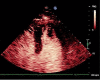

Left ventricular thrombosis is a known complication of myocardial infarction. COVID 19 has been shown to produce a procoagulant state resulting in venous and less commonly arterial thrombosis. Here, we describe a patient who presented with a non-ST elevation myocardial infarction (NSTEMI), in the context of a COVID 19 infection. This NSTEMI resulted in the formation of a large pedunculated apical thrombus, which was initially managed conservatively, however ultimately required surgical thromboembolectomy. Access to the left ventricle was gained via the transaortic route in order to avoid ventriculotomy in a patient with a reduced LV systolic function. Post-operative imaging confirmed complete resection of thrombus.